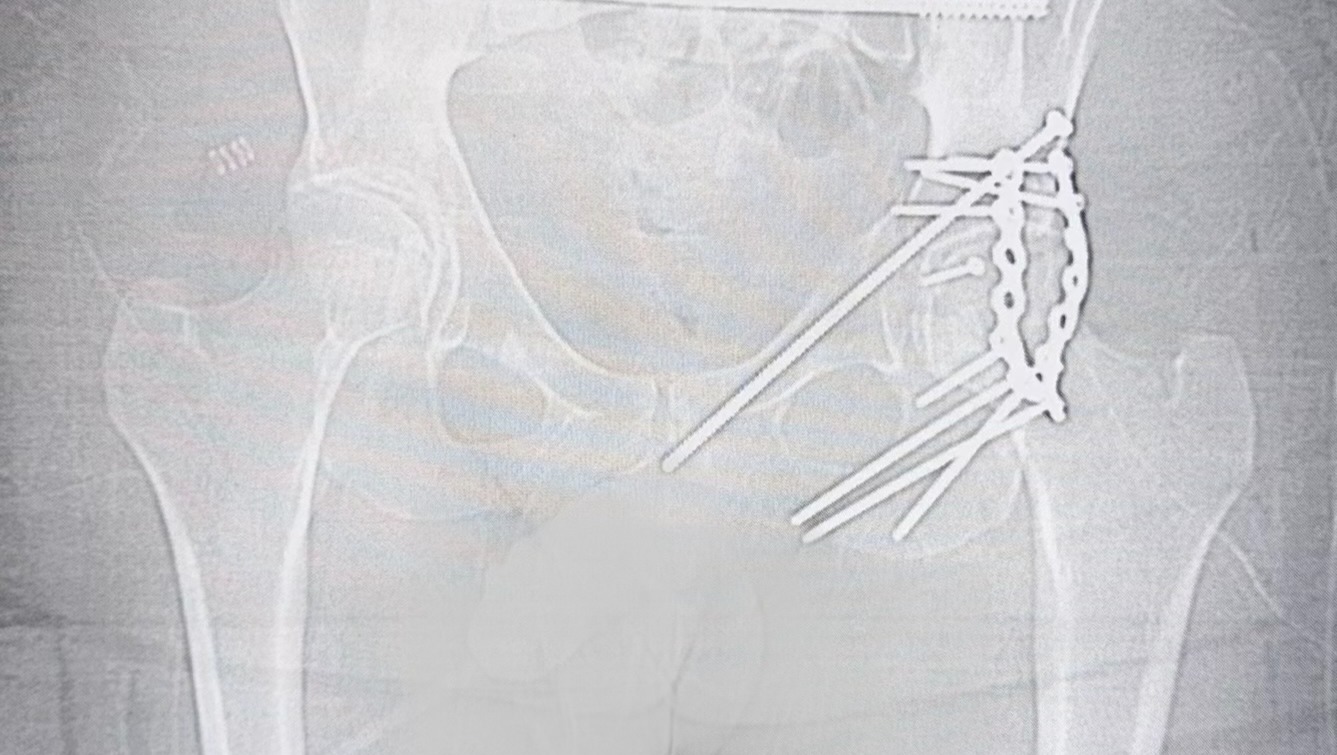

Lifesaving Surgery: Once he reached Boston, Greer was rushed into the MGH Trauma floor and immediately had holes drilled into his bones for traction to alleviate the pressure off his pelvis and hip to give additional time to organize the perfect team of surgeons for this complex injury. The next morning on March 9th, he had a marathon 10-hour emergency surgery. A specialized team of surgeons fought to piece him back together, installing the permanent rods, plates, and screws that now hold his pelvis, sacrum, and hips together.

- A “mangled” pelvis

- Broken, severely separated sacrum

- Drastically damaged, shattered hip

- Total leg dislocation of the other femur